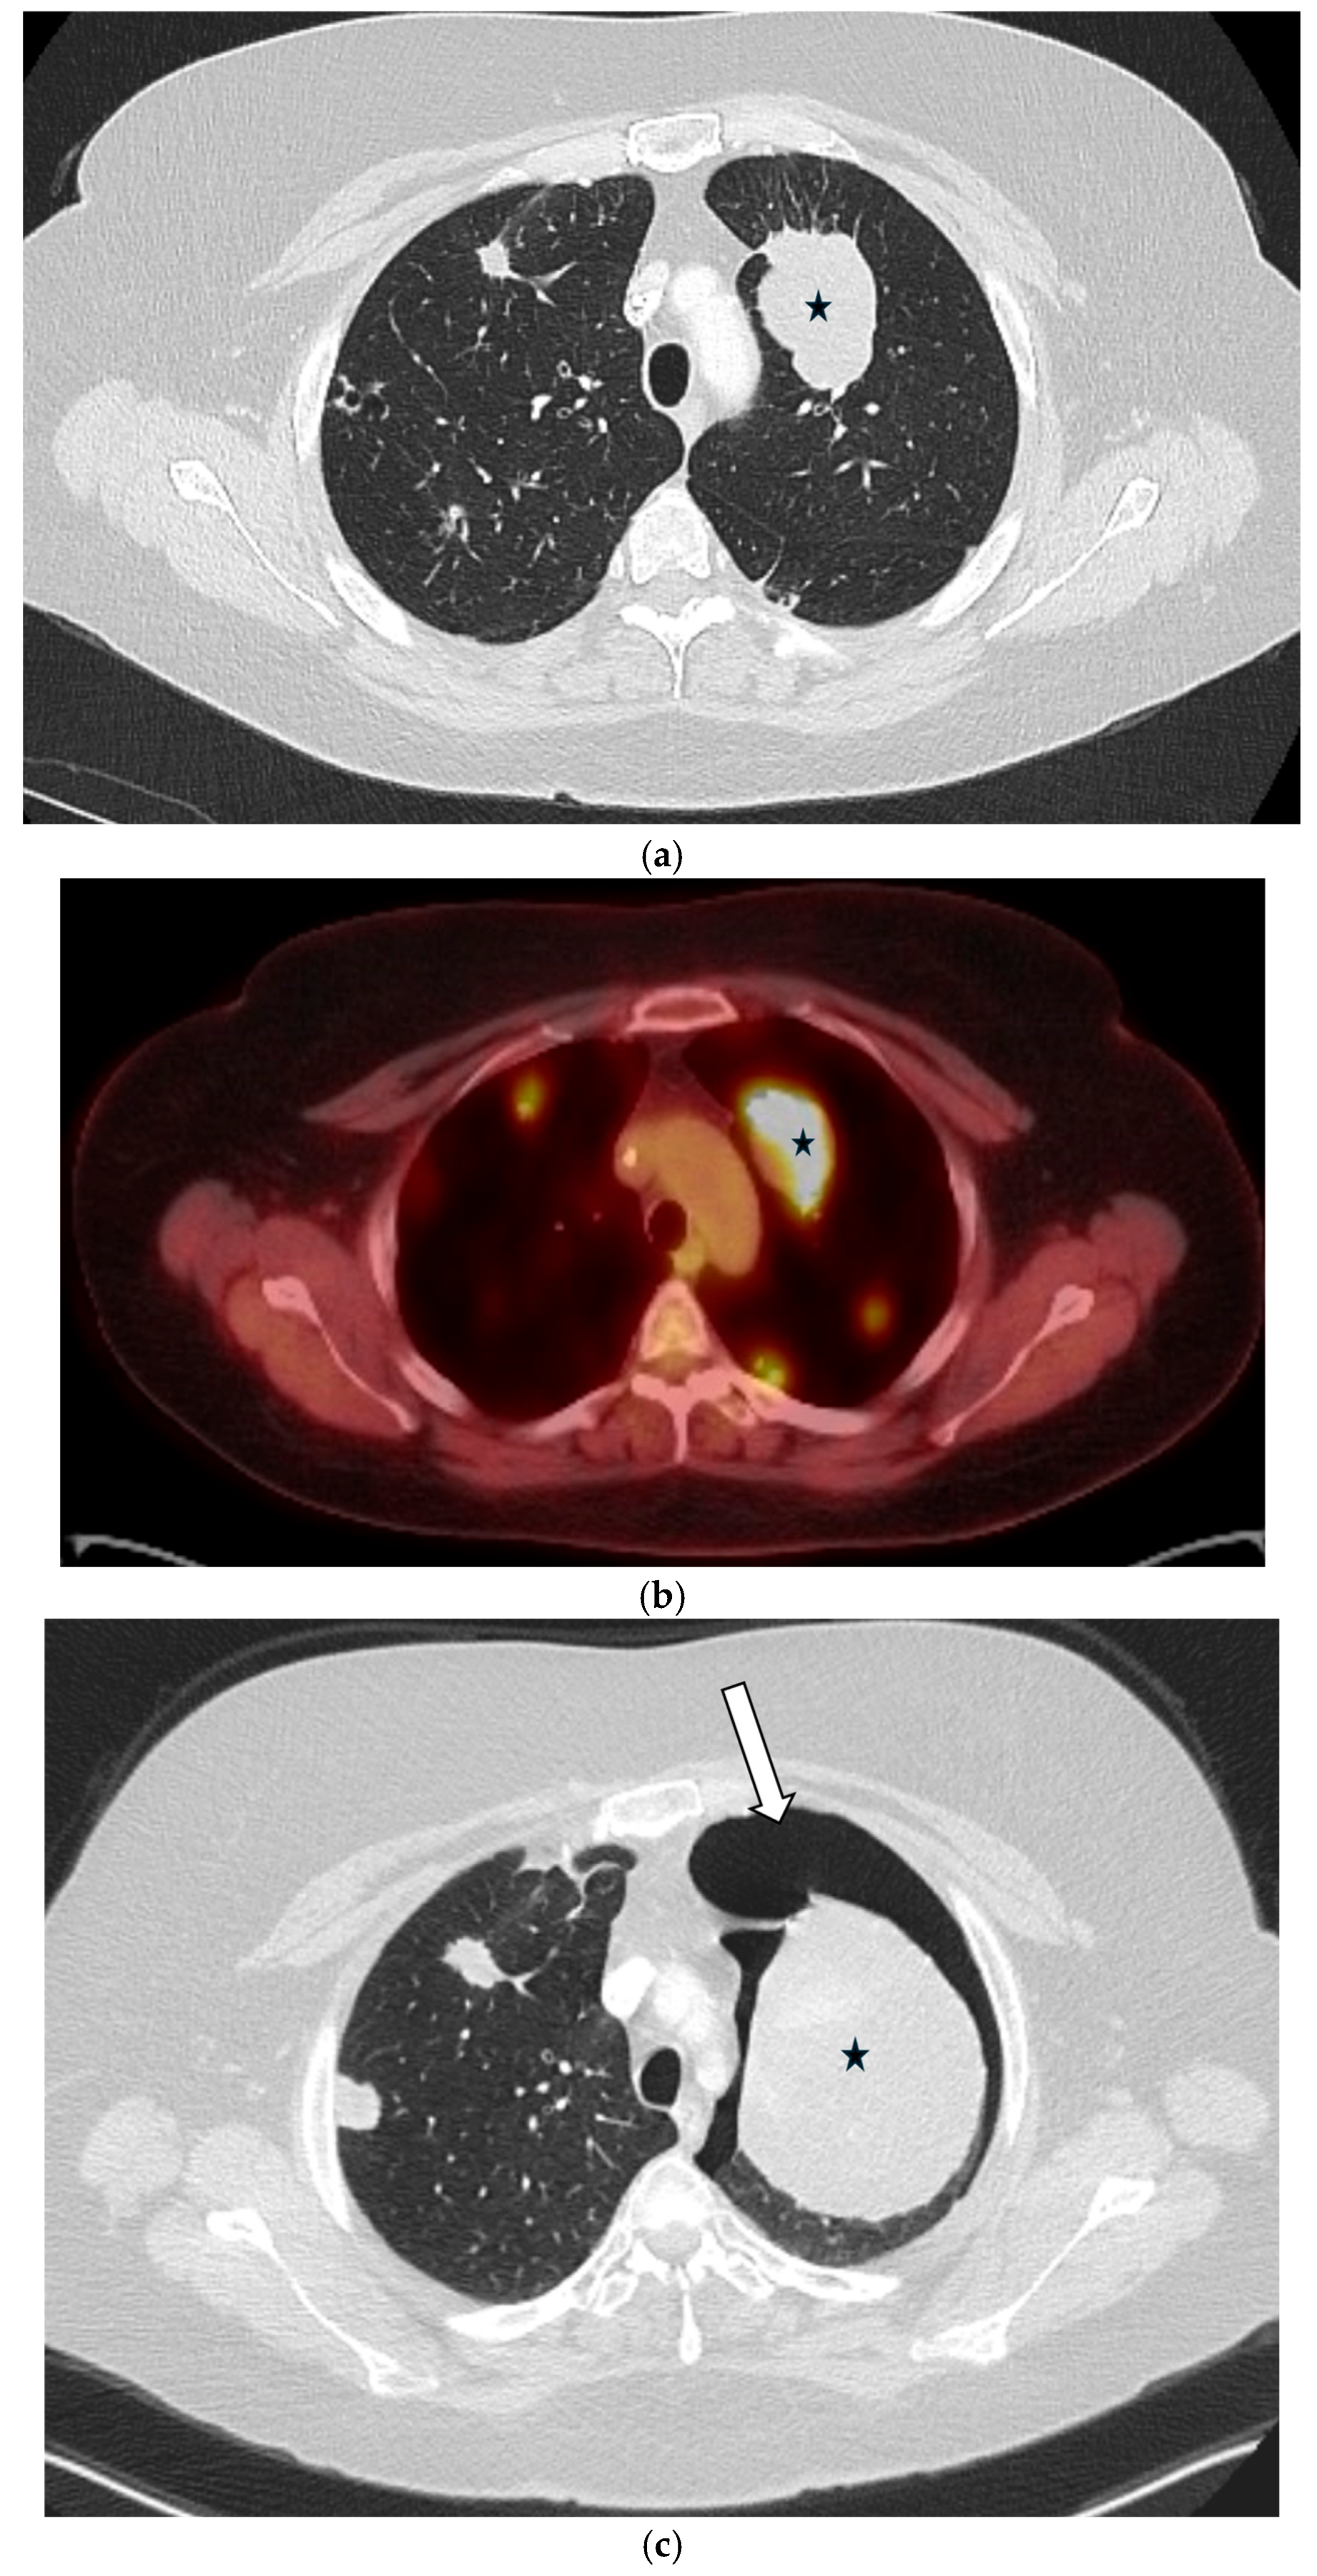

5.3. Malignancies

5.4. Interstitial Lung Diseases (ILDs)